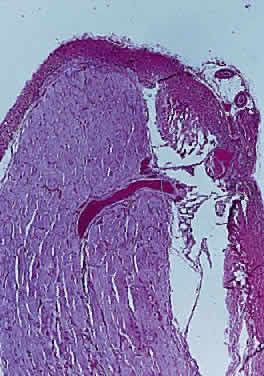

Injury to the retina or any peripheral portion of the optic nerve results in rapid ascending atrophy of the central portion. Initially, the axons at the peripheral portion swell. Retrograde degeneration of the axon then occurs, with loss of retinal ganglion cells. Clinically, there is pallor of the optic disc (Fig. 27), and early decreased fluorescence is seen with angiography. The atrophic optic nerve is surrounded by a loose sheath (Fig. 28). Microscopically, there is shrinkage of the nerve parenchyma secondary to axonal and myelin loss and gliosis (Fig. 29). Corpora amylacea accumulate in the subpial and perivascular areas (Fig. 30). With shrinkage of the nerve, the subarachnoid space is widened and the pial strands and arteriolar walls are thickened. Atrophy that is secondary to glaucoma is initially seen in the prelaminar region. Loss of astrocytes and axons results in baring of the lamina and deep excavation of the optic cup (Figs. 31 and 32).

Fig. 29. Thick collagenous pial strands in atrophic optic nerve extend around central vessels (cross-section hematoxylin and eosin staining).